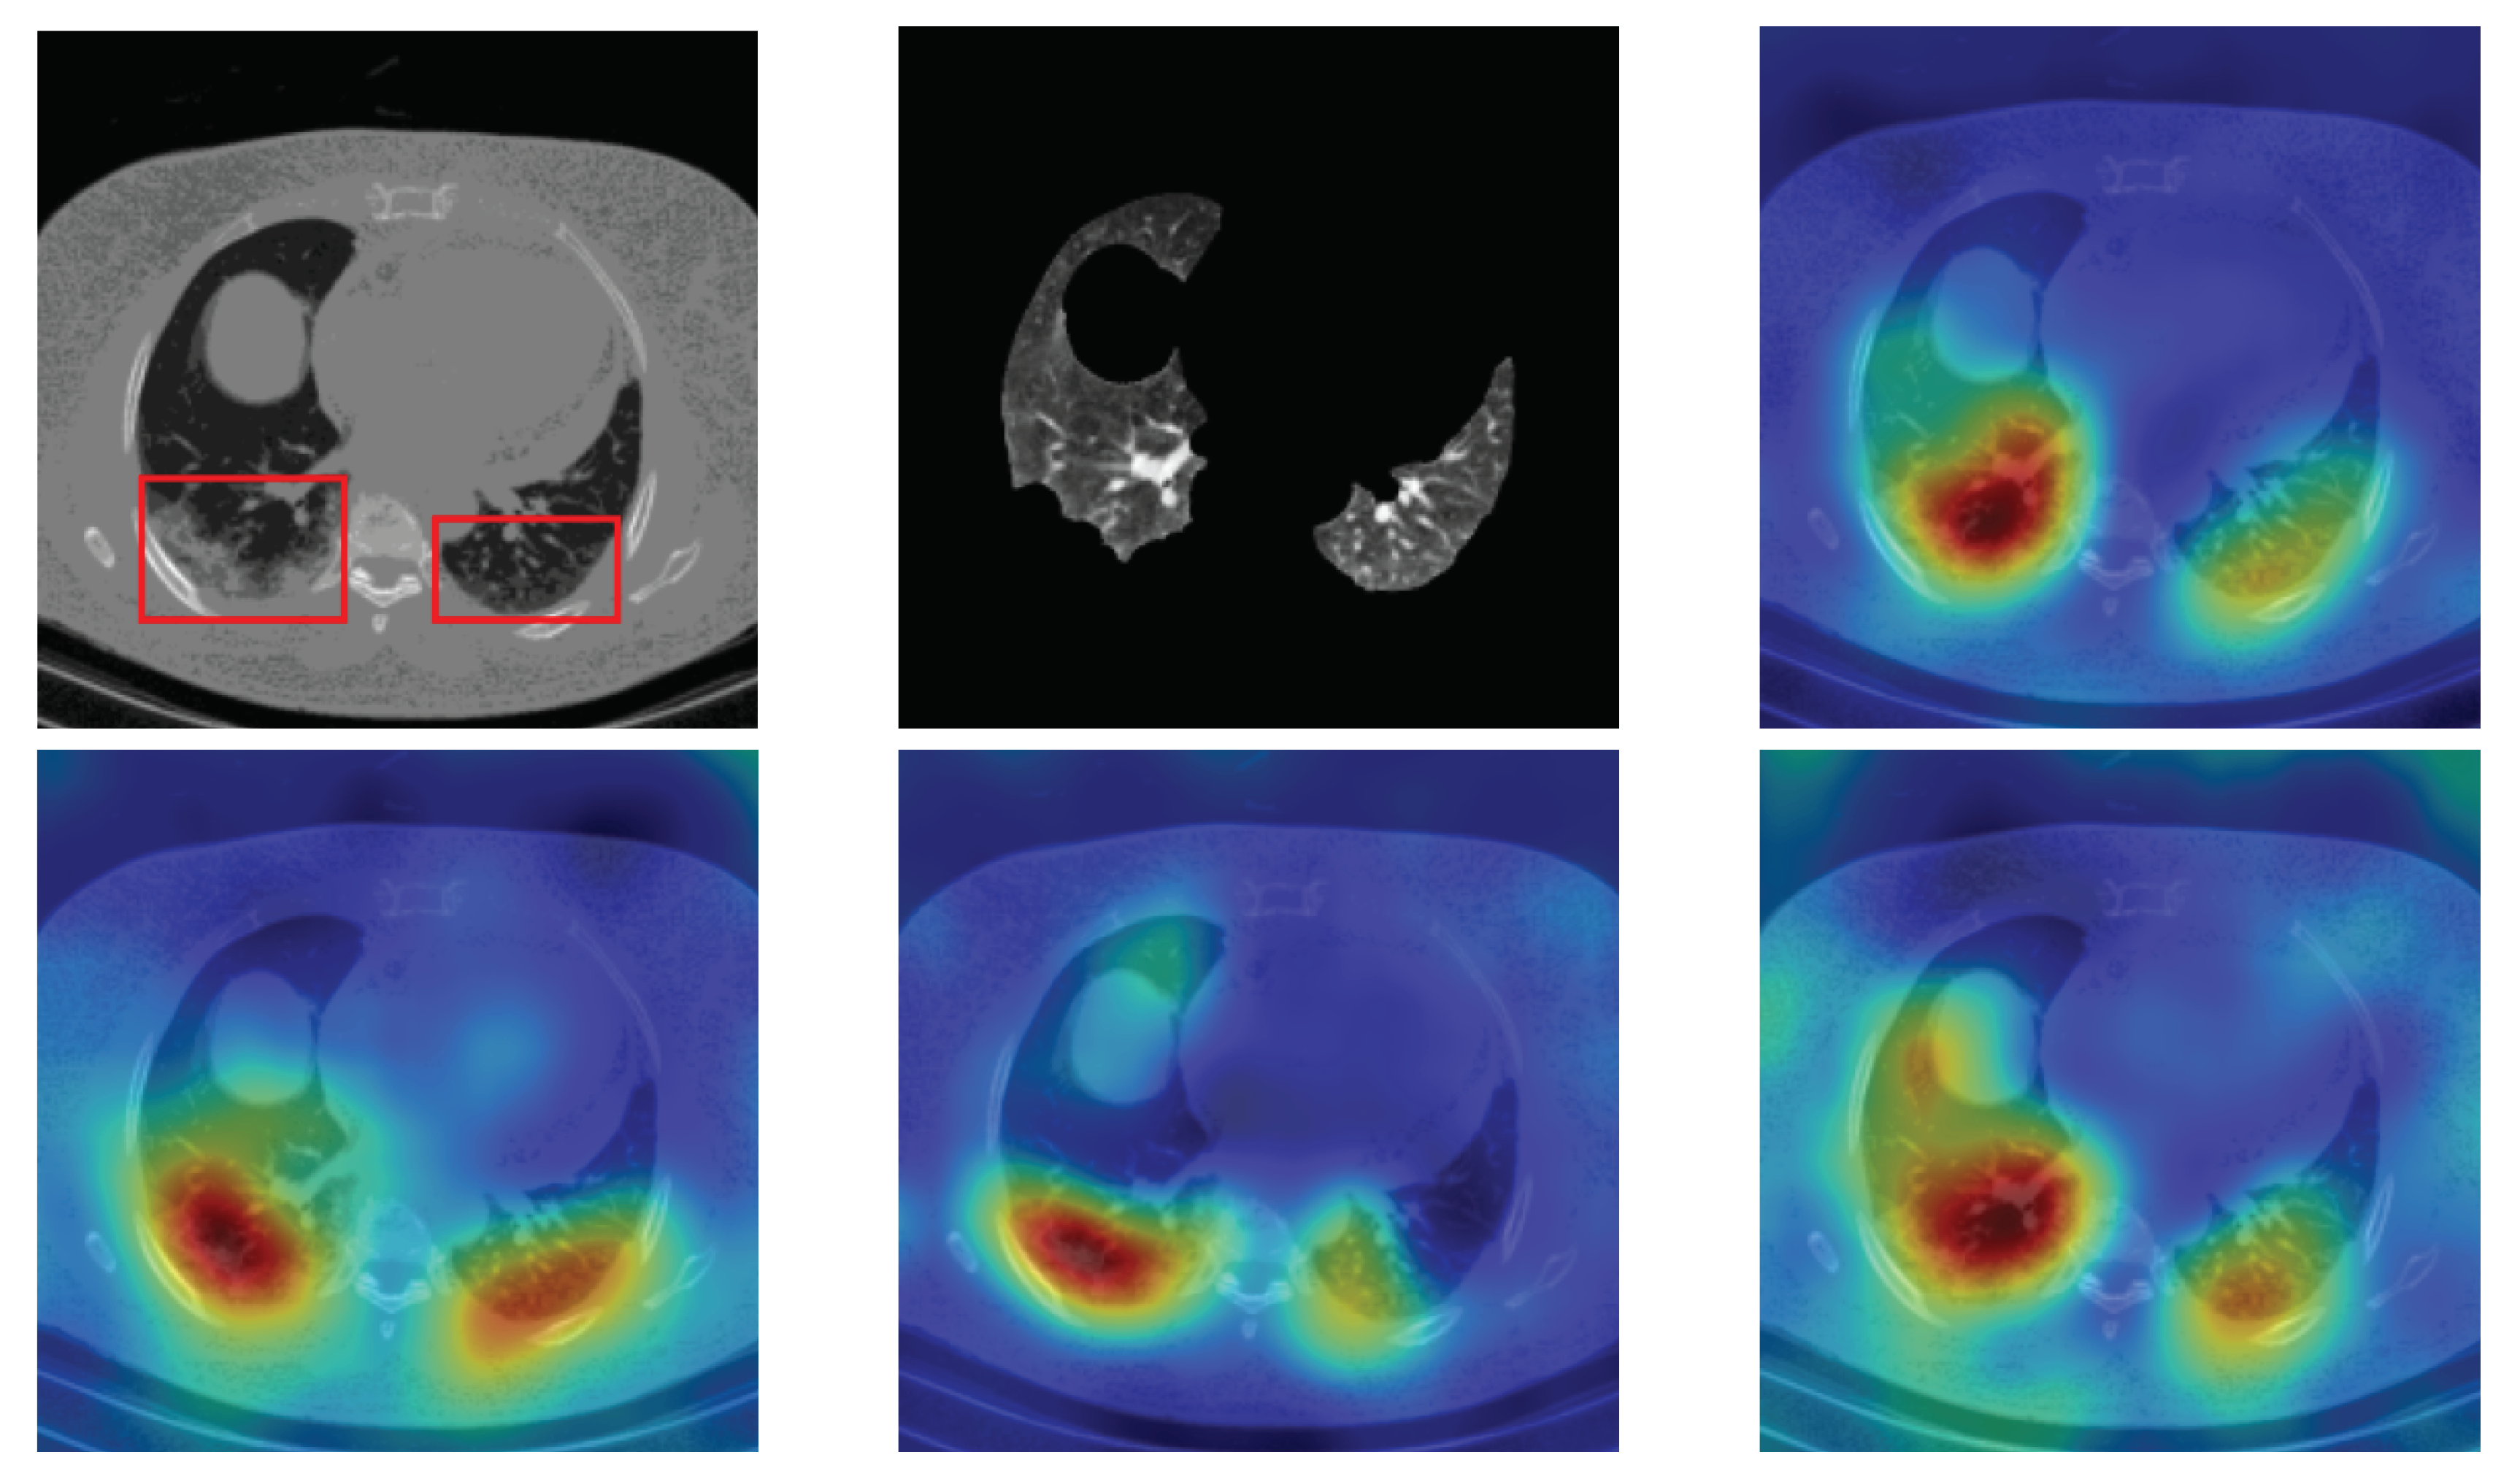

4.5. Heat Map

To have more intuition about the most important lung regions that the CNN architectures consider to classify the slice images, we used the randomized input sampling for explanations (RISE) approach [37]. Figure 13, Figure 14 and Figure 15 consist of two heat map examples of COVID-19, Cap, and normal cases, respectively. In the first example from Figure 13, we notice that despite the lung segmentation being not fully correct (it misses a considerable part of the infected region), the four CNN architectures gave more importance to the infected regions and to the lung regions in general. In the second example from Figure 13, we observe that the lung lobes were precisely segmented, and the heat maps of the four CNN architectures were well defined the infected regions, especially the Wide-Resnet-50 architecture. From both Cap examples in Figure 14, we notice that despite the lung segmentation missing considerable infected parts as well as the lung lobe regions, the heat maps of all CNN architectures give more importance to the infected region and to the lung lobes in general. This proves that the trained CNN architecture is able to define the regions of interest even when the lung lobes segmentation is not good. For the normal slice examples in Figure 15, the trained CNN architectures gave more importance to the lung lobes, especially the lower region, since the infection usually occurs there. The heat maps of COVID-19, Cap, and normal cases prove that the CNN architectures learned precisely where to look to identify the infection from the slice images.

Figure 15.

RISE heat map examples of normal slice image using the trained multi-tasks CNN architectures (ResneXt-50, Densenet-161, Inception-v3, and Wide-Resnet-50). The first example is shown in the first two rows, where the images represent the input slice image and segmented lung lobes results, followed by the heat maps of ResneXt-50, Densenet-161, Inception-v3, and Wide-Resnet-50, respectively. The second example is in rows 3 and 4.